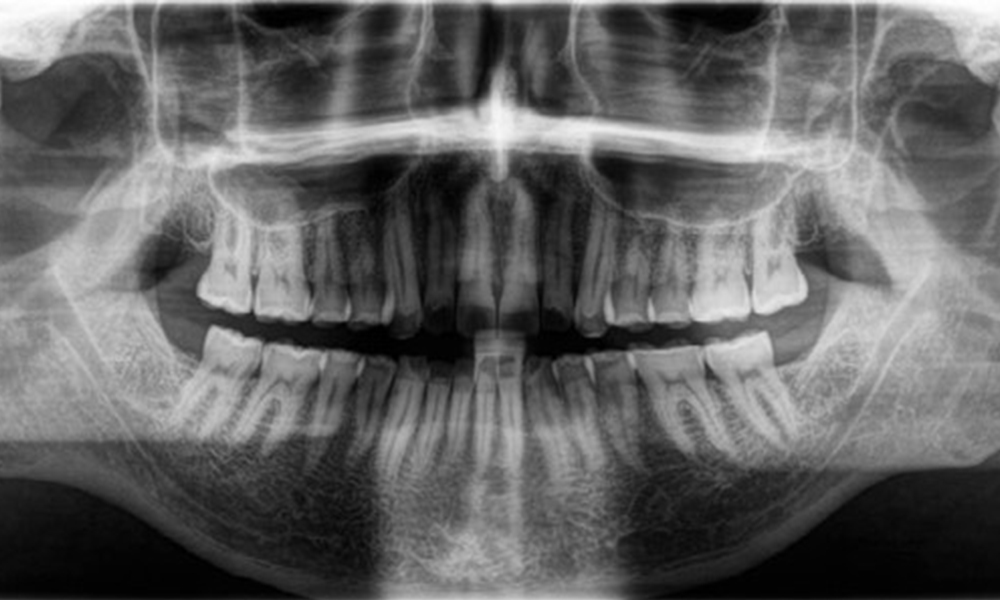

Radiological findings

Full complement of adult teeth with no caries or radiologically recognizable bone loss was observed (Fig. 6). Radiological enamel and cusp loss were particularly evident on 36 and 37.

Panoramic X-ray image

Fig. 6: Panoramic X-ray image, © Dr R. Krapf